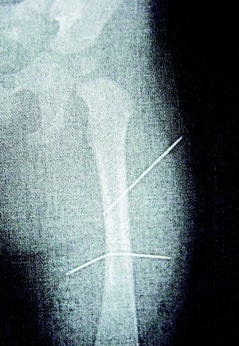

隔月27日,該女子又見外甥女哭鬧不停,拿蒼蠅拍朝著外甥女背部連打數(shù)十下,造成女娃背部瘀傷。經(jīng)女娃母親發(fā)現(xiàn)后送醫(yī)救護(hù),院方為女童進(jìn)行X光片照射后,才發(fā)現(xiàn)女娃左大腿里竟有兩根縫衣針。